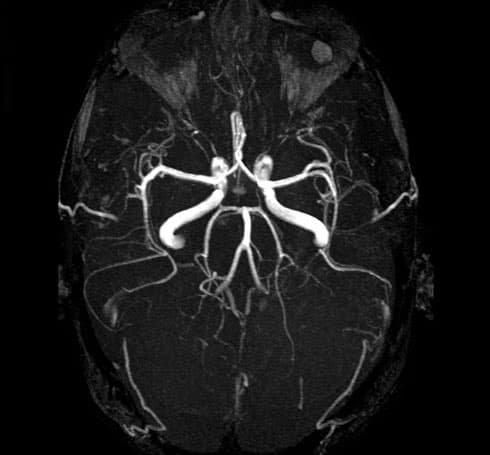

Brain arterial angio MRI (MR Angiography) is an advanced magnetic resonance method that provides detailed and non-invasive imaging of the arteries that feed the brain. This examination is of great importance in the diagnosis of stenosis, occlusion, aneurysms, arteriovenous malformations (AVM), and congenital vascular anomalies in the brain vessels. Brain arterial MR angiography is frequently preferred in cases such as headache, dizziness, sudden vision loss, suspected stroke, and transient ischemic attack. It is a safe imaging method as it does not contain radiation. It can often be performed without contrast material, and in necessary cases, vascular structures can be evaluated more clearly with contrast-enhanced brain angiography. Brain arterial angio MRI is more comfortable and risk-free compared to classical angiography. The procedure is painless and usually completed in a short time. Brain arterial angio MRI is an important diagnostic tool for early diagnosis and accurate treatment planning.